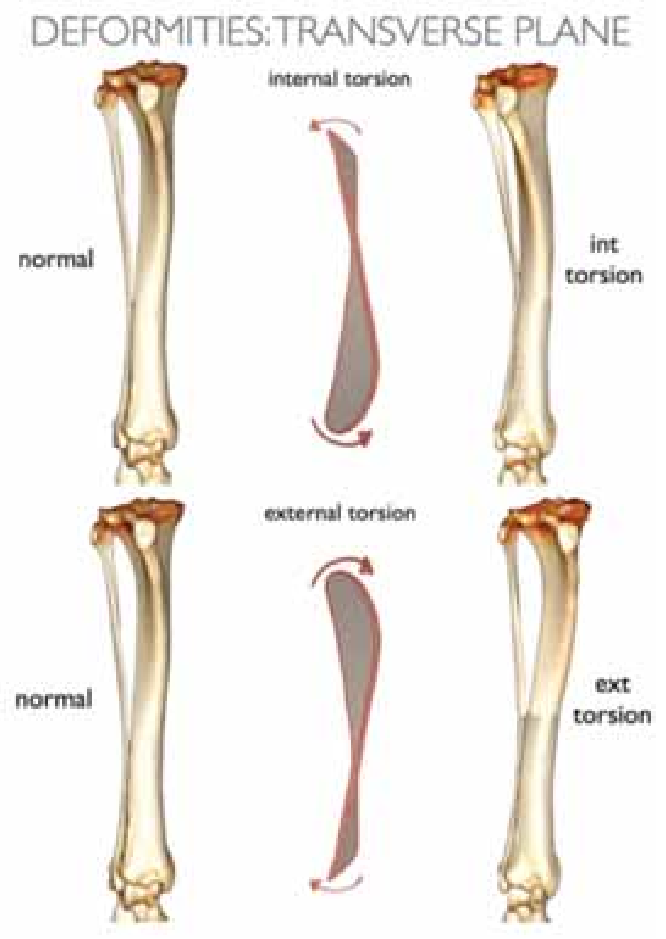

deformitet i koronalt och sagittalt plan på min felläkt tibia, finns det flera plan att tänka på hur skiljer jag de åt, vad är koronalt och sagittalt plan

Koronalt och sagittalt plan är två av kroppens huvudsakliga anatomiska plan som används för att beskriva riktning och deformiteter. De skiljer sig åt i hur de delar kroppen och hur en felställning i tibia kan yttra sig i varje plan.

Här är en tydlig förklaring:

🧠 Vad är koronalt och sagittalt plan?

- Koronalt plan (även kallat frontalplan):

- Delar kroppen i fram- och baksida.

- Tänk dig ett snitt som går från sida till sida, som om du delar kroppen mellan ansikte och bakhuvud.

- En deformitet i koronalt plan innebär att benet är böjt åt sidan – exempelvis valgus (utåt) eller varus (inåt) felställning.

- Sagittalt plan:

- Delar kroppen i höger och vänster sida.

- Tänk dig ett snitt som går från fram till bak, som om du delar kroppen mellan höger och vänster.

- En deformitet i sagittalt plan innebär att benet är böjt framåt eller bakåt – exempelvis rekurvatum (bakåtböjning) eller prokurvatum (framåtböjning).

🦵 Deformitet i tibia – vilka plan är relevanta?

Vid en felläkt tibia kan deformiteten uppträda i flera plan:

| Plan | Typ av deformitet | Beskrivning |

|---|---|---|

| Koronalt | Varus / Valgus | Benet böjer inåt eller utåt |

| Sagittalt | Prokurvatum / Rekurvatum | Benet böjer framåt eller bakåt |

| Transversalt | Rotation (inåt/utåt) | Benet är vridet kring sin längdaxel |

| Longitudinellt | Förkortning / förlängning | Benet är kortare eller längre än normalt |

🔍 Hur skiljer du dem åt kliniskt?

- Observation och röntgen i olika plan är avgörande:

- Frontal röntgen → visar koronala deformiteter.

- Sidobild → visar sagittala deformiteter.

- CT eller klinisk undersökning → visar rotationsfel.

- Symtom och gångmönster kan också ge ledtrådar:

- Valgus/varus påverkar knäets belastning.

- Prokurvatum/rekurvatum påverkar gångens stabilitet.

- Rotation kan ge snubbelkänsla eller felaktig fotisättning.